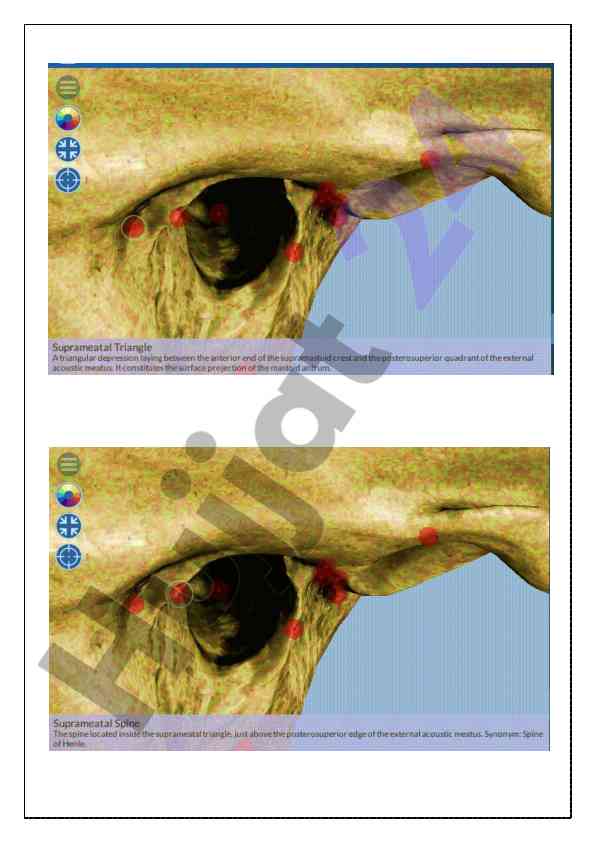

Kalla skeleti va chakka suyagi haqida umumiy ma'lumotlar taqdim etilgan o‘quv qo‘llanma. Anatomiyaga oid asosiy tushunchalar va strukturalar izohlangan.